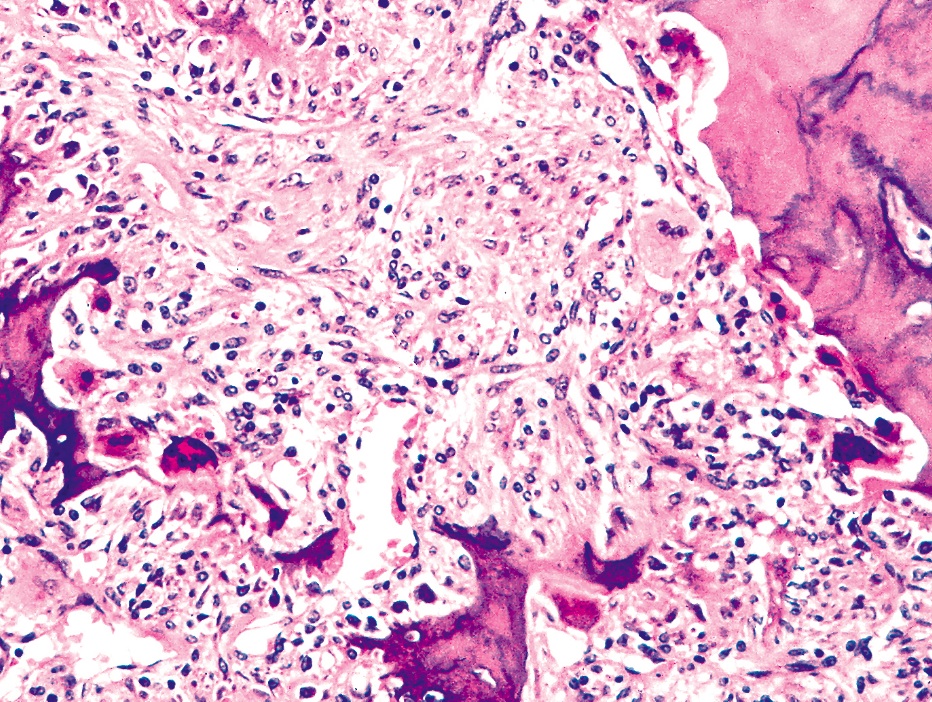

Paget's Disease Pathology Outlines . Underlying breast lesion is usually a. Paget disease's pathological process occurs in 4 stages. It begins with osteoclastic activity, followed by a hybrid osteoclastic/osteoblastic. Paget's disease of the breast is an uncommon manifestation of underlying breast cancer in postmenopausal female patients. Paget disease versus melanoma versus squamous cell carcinoma in situ. Paget's disease is an idiopathic condition of abnormal bone remodeling with normal bone being replaced through an active. Paget disease of bone most commonly presents with a pathologic fracture but can present as generic bone pain. Extramammary paget disease (empd) is defined as intraepidermal adenocarcinoma and may originate from the.